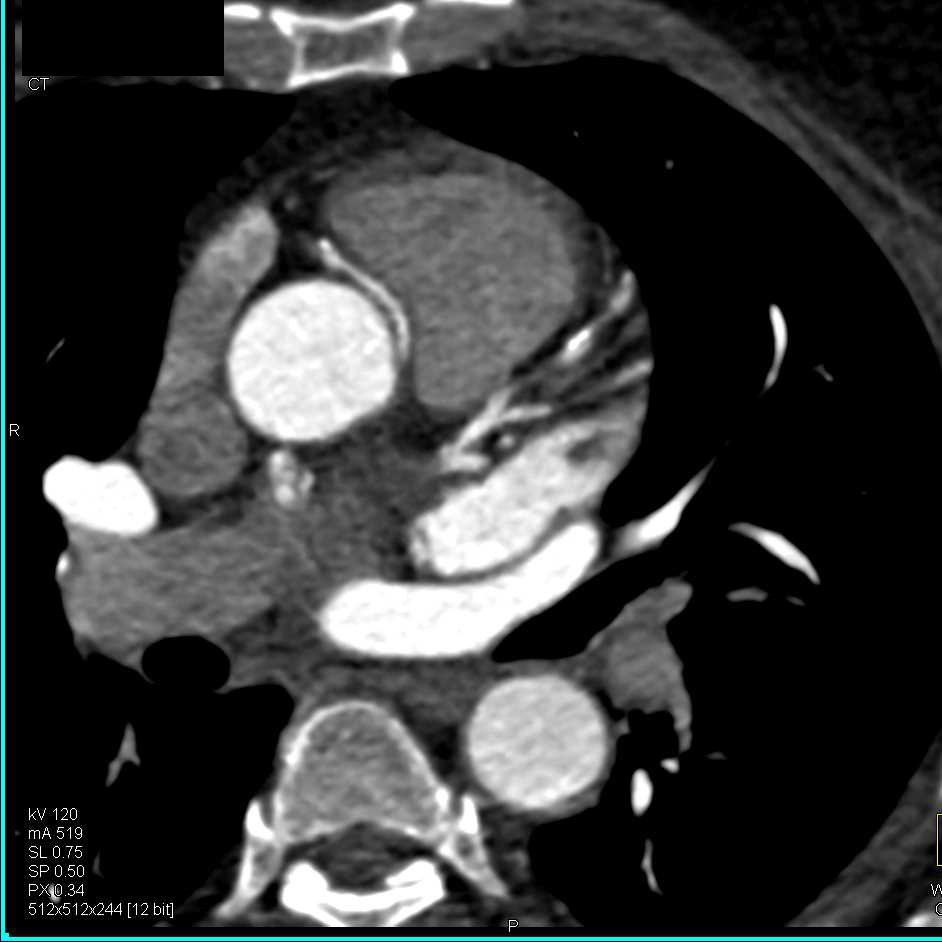

Pseudoaneurysm off the Ascending Aorta